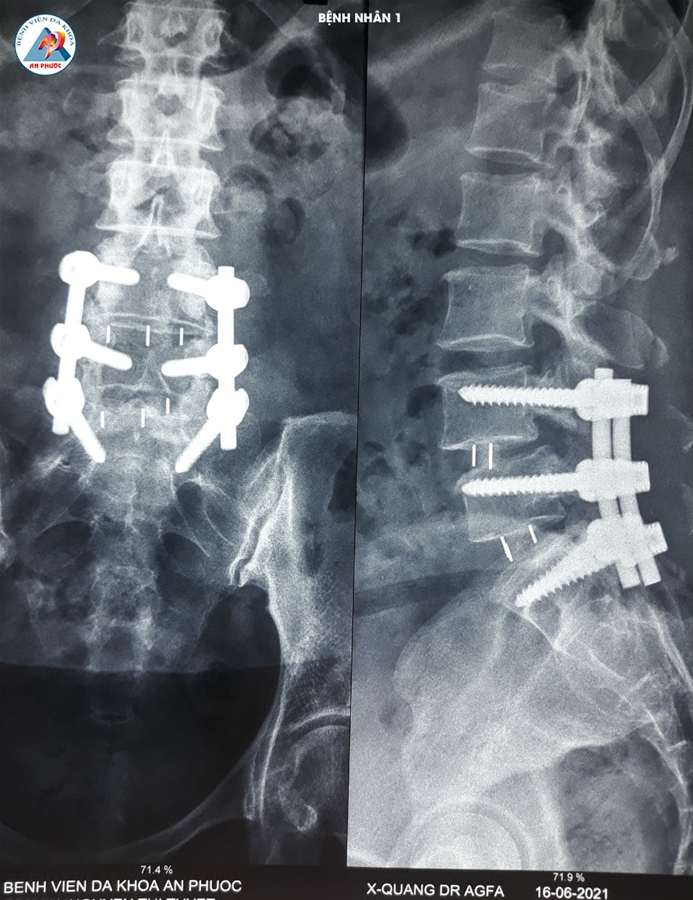

Trường hợp 1: Bệnh nhân nữ, 58 tuổi, ngụ tại Hàm Thuận Nam, Bình Thuận. Vào viện trong tình trạng đau lưng, tê, yếu hai chân hơn 10 năm. Bệnh nhân đã được điều trị nội khoa, kết hợp với tập vật lý trị liệu nhiều lần, ở nhiều Bệnh viện khác nhau, nhưng bệnh không giảm.

Sau khi được Bác sĩ chuyên khoa khám lâm sàng và cận lâm sàng (chụp MRI, XQ CSTL (có Film). Bệnh nhân được chỉ định phẫu thuật: Lấy nhân đệm và làm cứng CSTL bằng nẹp vis, thay đĩa đệm nhân tạo.

Sau 07 ngày phẫu thuật, bệnh nhân hết tê hai chân. Đi, đứng, vận động hai chân bình thường.